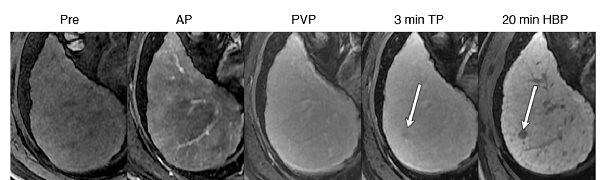

病例展示:钆塞酸二钠早期肝癌诊断优势,下图显示钆塞酸二钠对于普通增强显示不清的早期肝癌有明显优势(白箭头所示早期肝癌病灶肝胆期为低信号)。